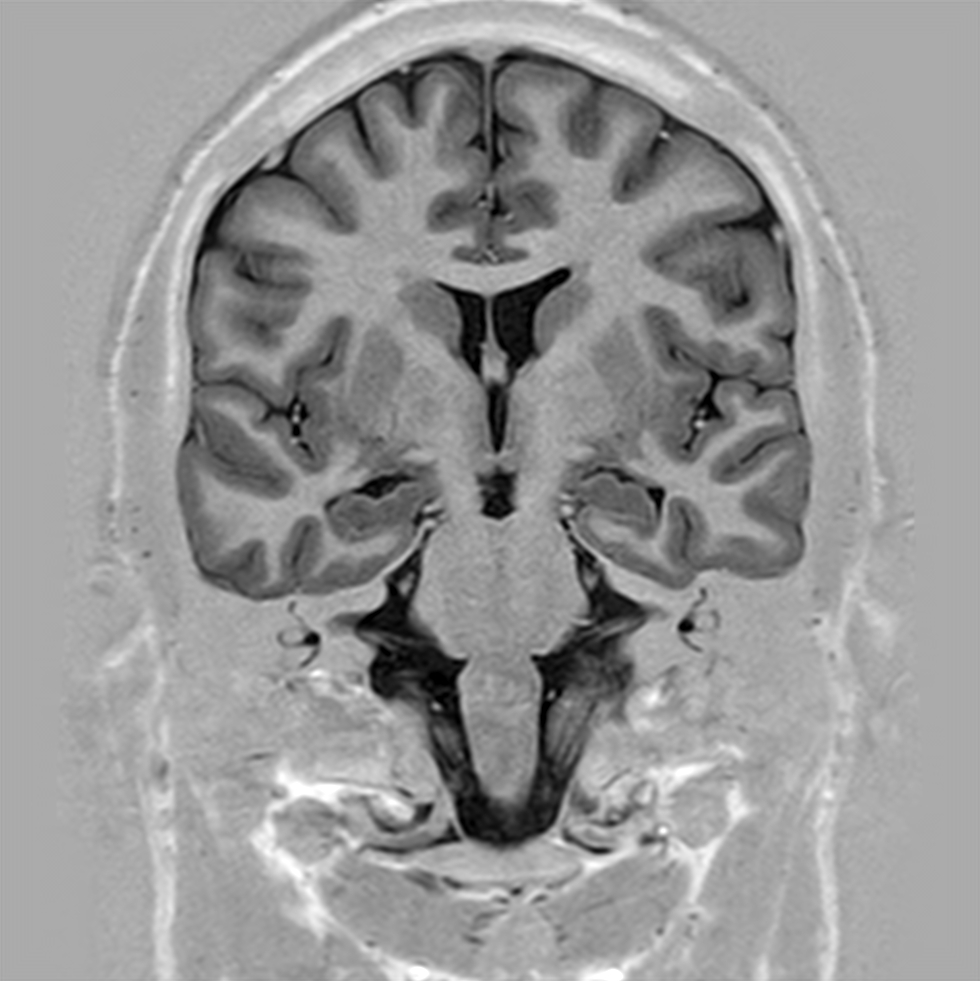

T1w 3D FFE (coronal reformat)